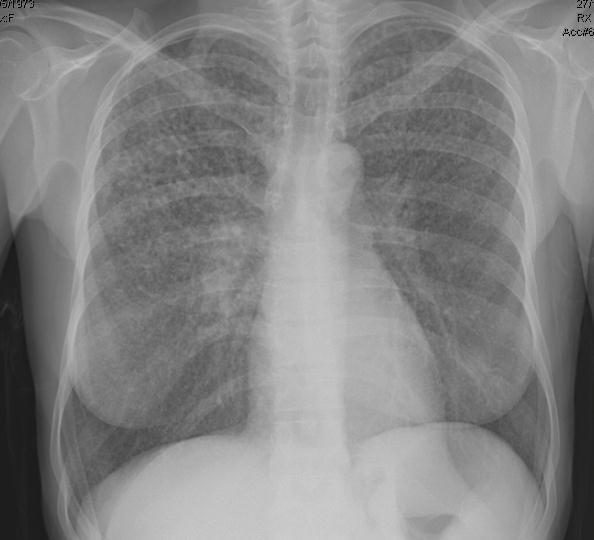

Radiografia